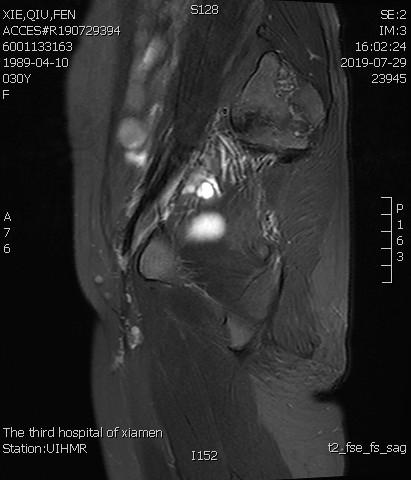

术后3个月复查MRI显示子宫明显缩小,前壁病灶萎缩坏死

- 术前MRI检查显示子宫明显增大。

术前MRI检查显示子宫明显增大

术后复查MRI显示子宫明显缩小,腺肌瘤明显坏死吸收